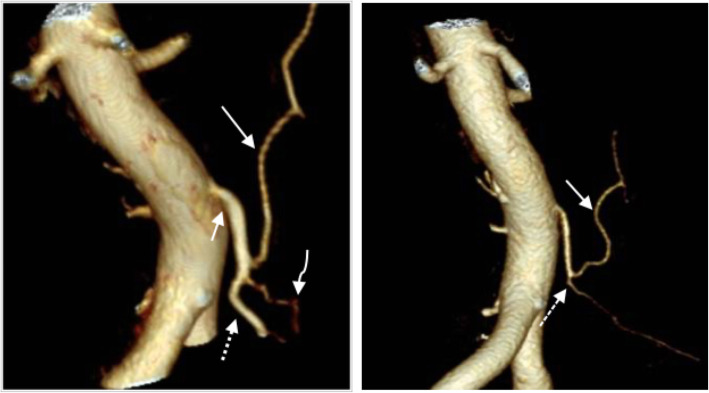

The purpose of the supplementary arterial phase was to map the remaining mesenteric arterial anatomy in order to visualize whether the level of ligation of the IMA was located proximal or distal to the left colic artery. Intra-individual comparisons of the preoperative CT examinations were sometimes used to aid the evaluation. The level of ligation was determined as low if the left colic artery was preserved and high if it could not be identified (Figs. 1 and 2).

Fig. 1.

The left image shows the preoperative vascular anatomy with the inferior mesenteric artery (short arrow), the left colic artery (long arrow), the sigmoidal arteries (curved arrow), and the superior rectal artery (dashed arrow). The right image shows a postoperative image where the superior rectal artery cannot be found. The dashed arrow marks the ligation level caudally to the remaining left colic artery (solid arrow) and the sigmoidal arteries